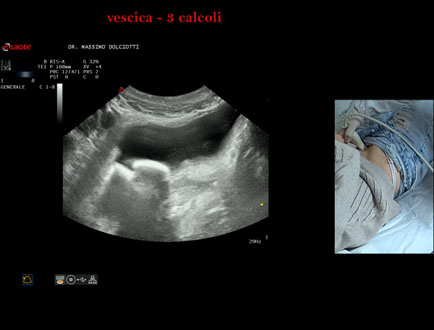

Data inserimento: 21/10/2025

Ecografia del: 15/10/2025

Strumento: Esaote MyLab Eight

Sonda: Convex Multifrequenza 1-8 MHz

Età Paziente: F 45 anni

Motivazione dell'esame: da alcuni mesi, disuria ed infezioni urinarie recidivanti.

Commento all'esame: le immagini ed il video documentano 3 immagini iperecogene, con cono d'ombra posteriore, da ricondurre a litiasi multipla della vescica.

Conclusioni: 3 calcoli della vescica (3 bladder stones).

Presentazione: Dr. Massimo Dolciotti - Ancona

Elaborazione digitale: Andrea Dini - Ancona

VISUALIZZA IL VIDEO